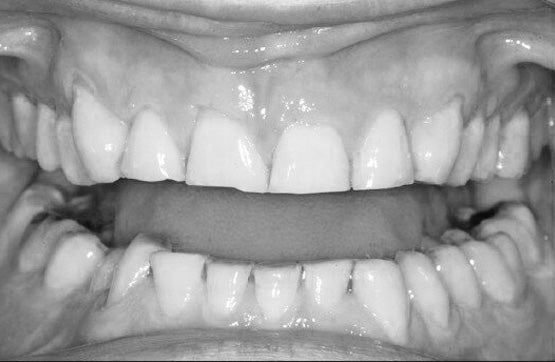

Le bruxisme est un trouble caractérisé par un serrement ou un grincement involontaire et répétitif des dents, principalement pendant le sommeil. Il peut entraîner une usure prématurée de l'émail dentaire, des douleurs à la mâchoire, des maux de tête, des troubles du sommeil et même des lésions aux gencives ou aux muscles faciaux. Bien que les causes exactes du bruxisme ne soient pas toujours claires, le stress, l'anxiété et les problèmes d'occlusion dentaire sont souvent cités comme facteurs contributifs.

L'avantage principal des gouttières occlusales réside dans leur capacité à protéger les dents contre l'usure excessive causée par le bruxisme. En créant un espace entre les arcades supérieure et inférieure, ces dispositifs absorbent les forces de friction et de compression générées par le grincement et le serrement des dents. Cela prévient l'amincissement de l'émail dentaire, les fissures, les éclats et l'exposition de la dentine sous-jacente.

Dans certains cas, le bruxisme peut être lié à des problèmes d'occlusion dentaire sous-jacents. En combinant le port d'une gouttière avec un traitement orthodontique visant à corriger l'alignement des dents, il est possible d'obtenir une amélioration durable des symptômes.